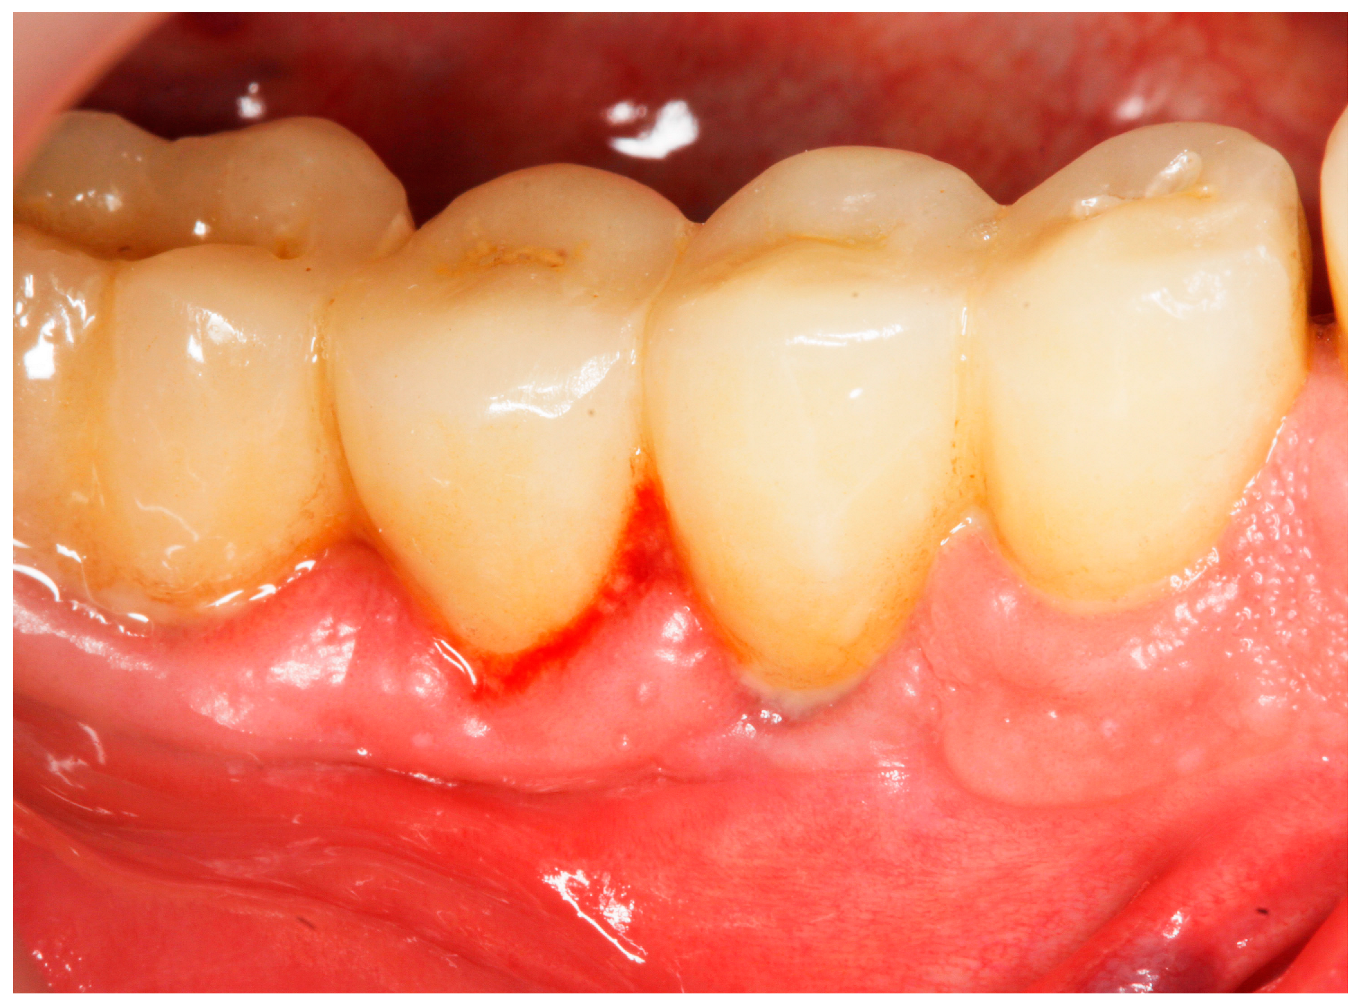

- Bleeding on probing (BoP) was recorded as 0 (no bleeding) or 1 (bleeding) after probing for PPD [15] (presence/absence of bleeding within 30 s following probing) (Figure 1);

- (3)

Baseline: Prior to PiM treatment, PMPR was performed in all subjects (Figure 3), for both teeth and implants. Each patient was assigned to one of the two treatment groups according to computer-generated randomization. One implant (the one with the greatest number of BoP points or the presence of a line of bleeding or profuse bleeding) with PiM in each patient was selected for the study. PMPR of the implants of interest was performed using an ultrasonic scaler with a plastic tip (Piezon® Master700 with Piezon® PI instrument, EMS, Nyon, Switzerland), and air polishing (Perioflow® handpiece, Airflow® PLUS powder, EMS, Nyon, Switzerland) was carried out at all sites. Piperacillin plus tazobactam gel Gelcide® (Italmed, Firenze, Italy) was prepared according to the manufacturer’s recommendations and was applied as follows: the solution was injected into the powder container, and the container was shaken until the solution became homogeneous. After mixing, the consistency of the mixture slightly increased, so it could be applied at the implant surface. Instrumentation was followed by subgingival application of the volatile mixture, depending on the patient’s group. For the Gelcide® group (test), topical application of Gelcide® was performed for the placebo group (control), topical application of a placebo (the volatile polymeric carrier alone) was carried out. The necessary quantity (not standardized) was then extracted from the mixed container with a syringe and inserted into the peri-implant sulcus at the apical extremity (Figure 4) until the excess became visible at the mucosal margin. Once the product had been applied, the excess was removed using a cotton ball.